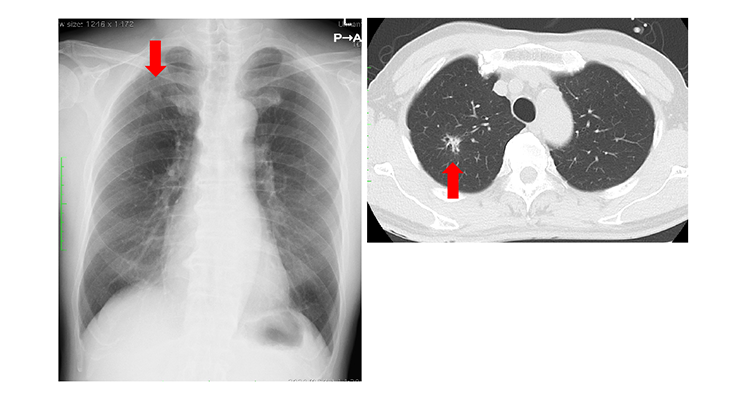

原発性肺癌(右上葉肺癌)の胸部レントゲン写真と胸部CT。矢印は原発性肺癌を示しています。

呼吸をする時に空気が通る道筋を気道(きどう)と呼びます。気道の中で気管支から肺胞に至る部分が肺と定義され、肺に発生するがんの全てが肺癌とされます。肺癌の原因として、現在のところはっきりしているのは喫煙です。今や日本人の二人にひとりががんになるとされていますが、2017年1年間に日本で12万4千人以上が肺癌になり (がん罹患数の第3位)、44,140件の手術が実施されています。肺癌の治療法は原則的には病期(病気の進行度)によって決められます。加えて、癌の特徴、年齢、これまでにかかった病気(既往症)、現在かかっている病気(併存症)、臓器(特に肺と心臓)の機能や健康状態に基づいて、慎重に治療法を選択します。肺癌の治療法には、外科療法、放射線療法、抗癌剤による化学療法、免疫療法、痛みや他の苦痛の緩和を目的とした緩和療法などがあります。手術は主としてI期とⅡ期に対して行われますが、Ⅲ期(癌がある側の縦隔リンパ節転移がある、あるいは周囲臓器に浸潤している場合)であっても手術療法を選択する場合があります。肺癌に対する標準術式は、癌の存在する肺葉の切除と所属リンパ節に転移がないかどうかを確認するためのリンパ節郭清術から成ります。I期及びⅡ期の肺癌では、主に胸腔鏡下手術あるいはロボット支援(ダヴィンチ)手術によりこの標準手術を行います。術後6〜7日で退院できる方が多いです。